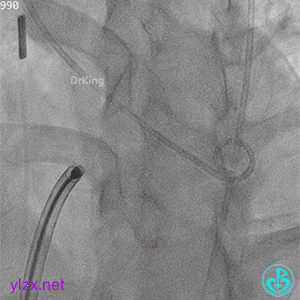

术中造影

结合实际术中造影,为大型膜部瘤室间隔缺损,左室入口直径12.79mm,右室出口直径为6.38mm,选择腰部直径为14的全降解封堵器进行封堵。

建立动静脉轨道

由导丝建立完整动静脉轨道,以便后续手术沿导丝轨道将全降解封堵器系统鞘管送入左心室。